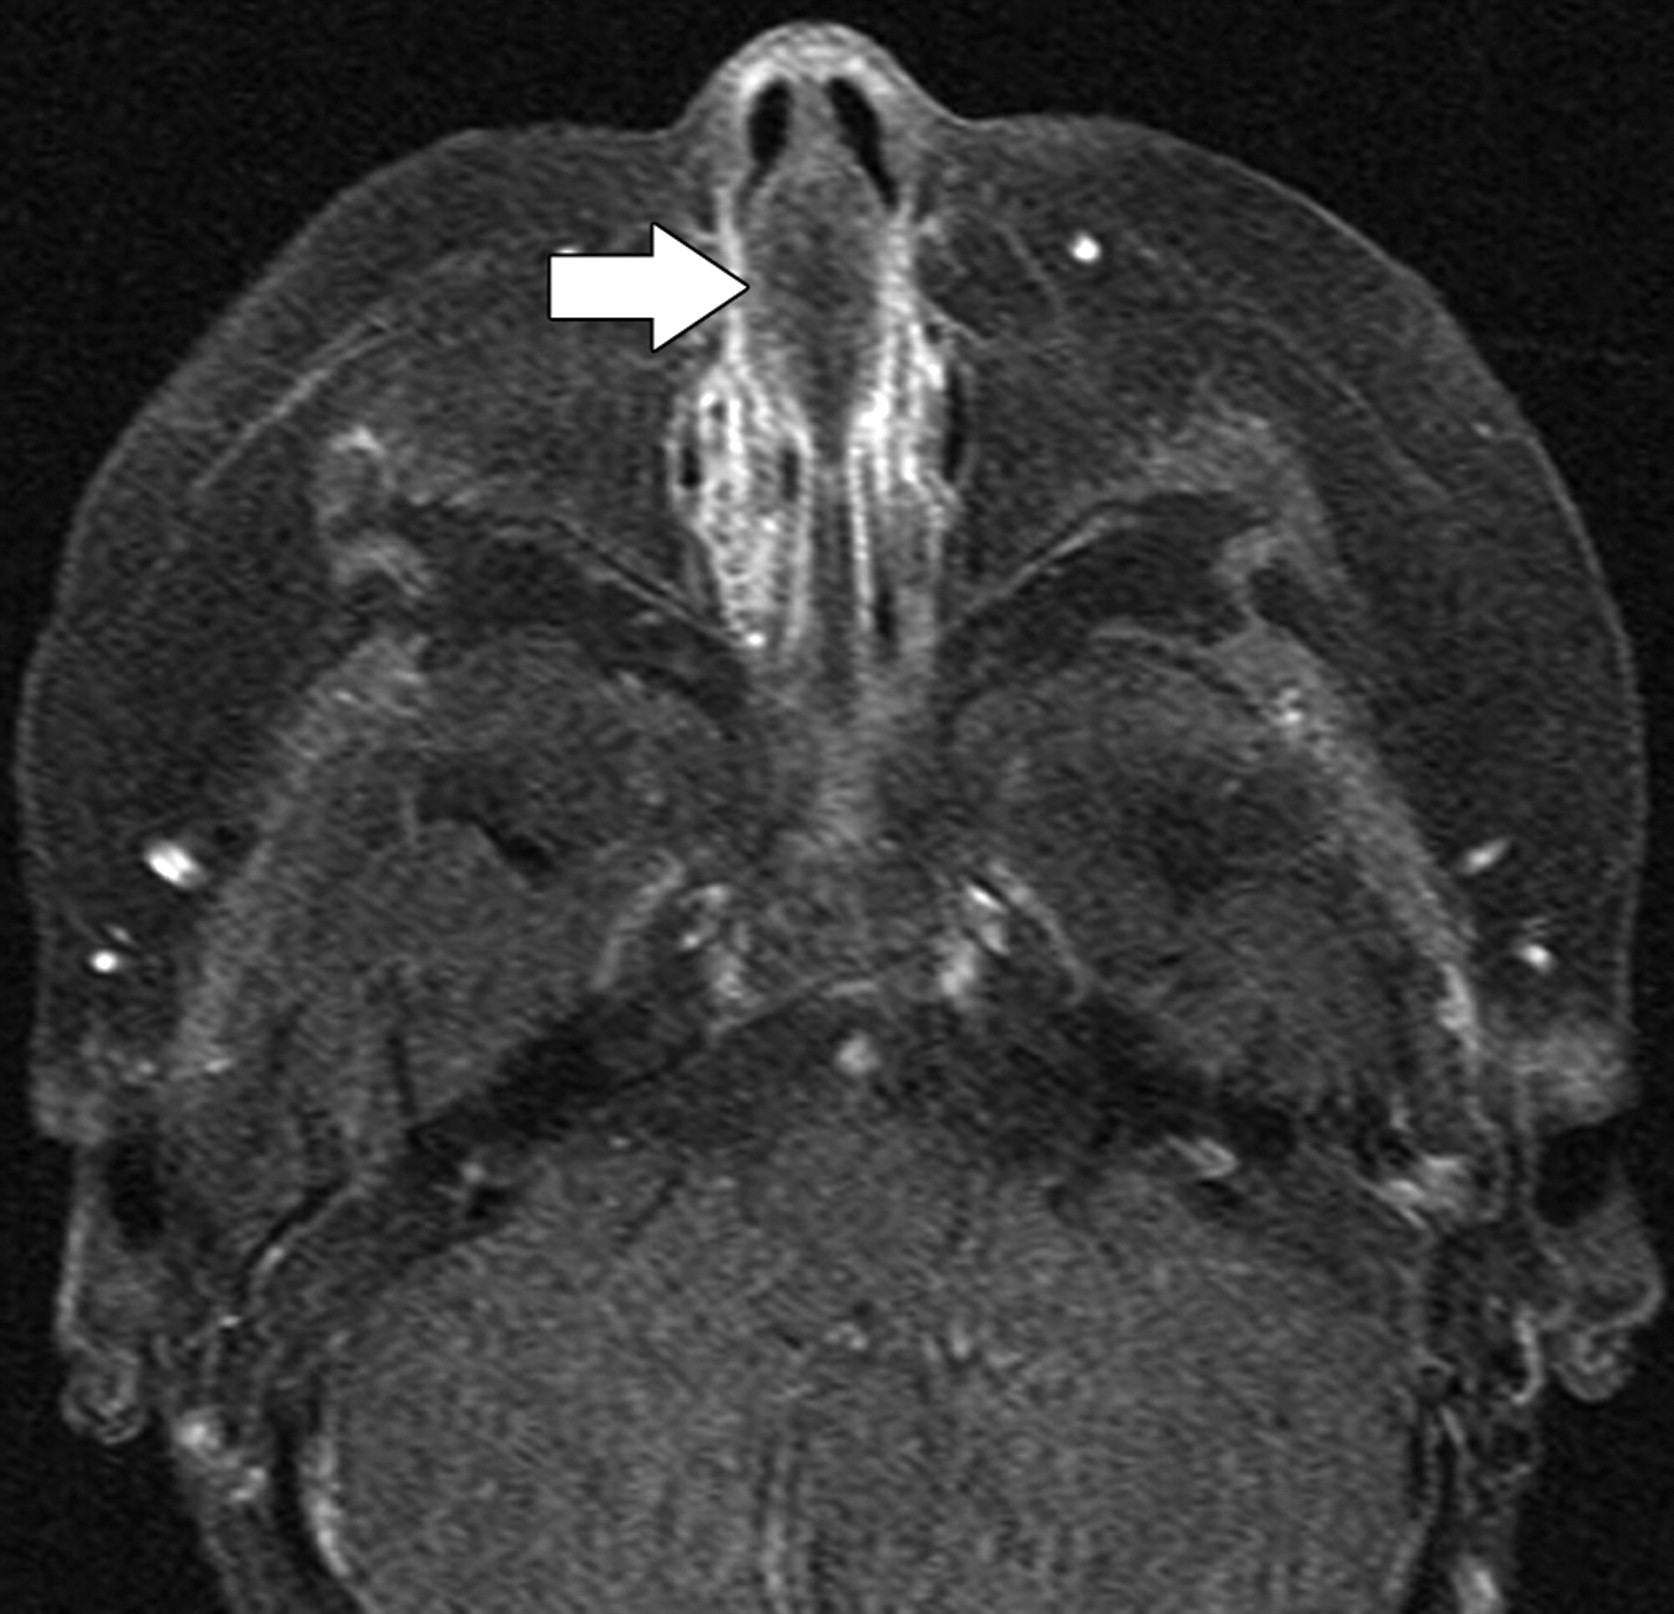

Пломбировочный материал.

Приложения:

1.g.slayd7_.jpg2.g.slayd8_.jpg3.g.slayd10.jpg4.g.slayd11.jpg